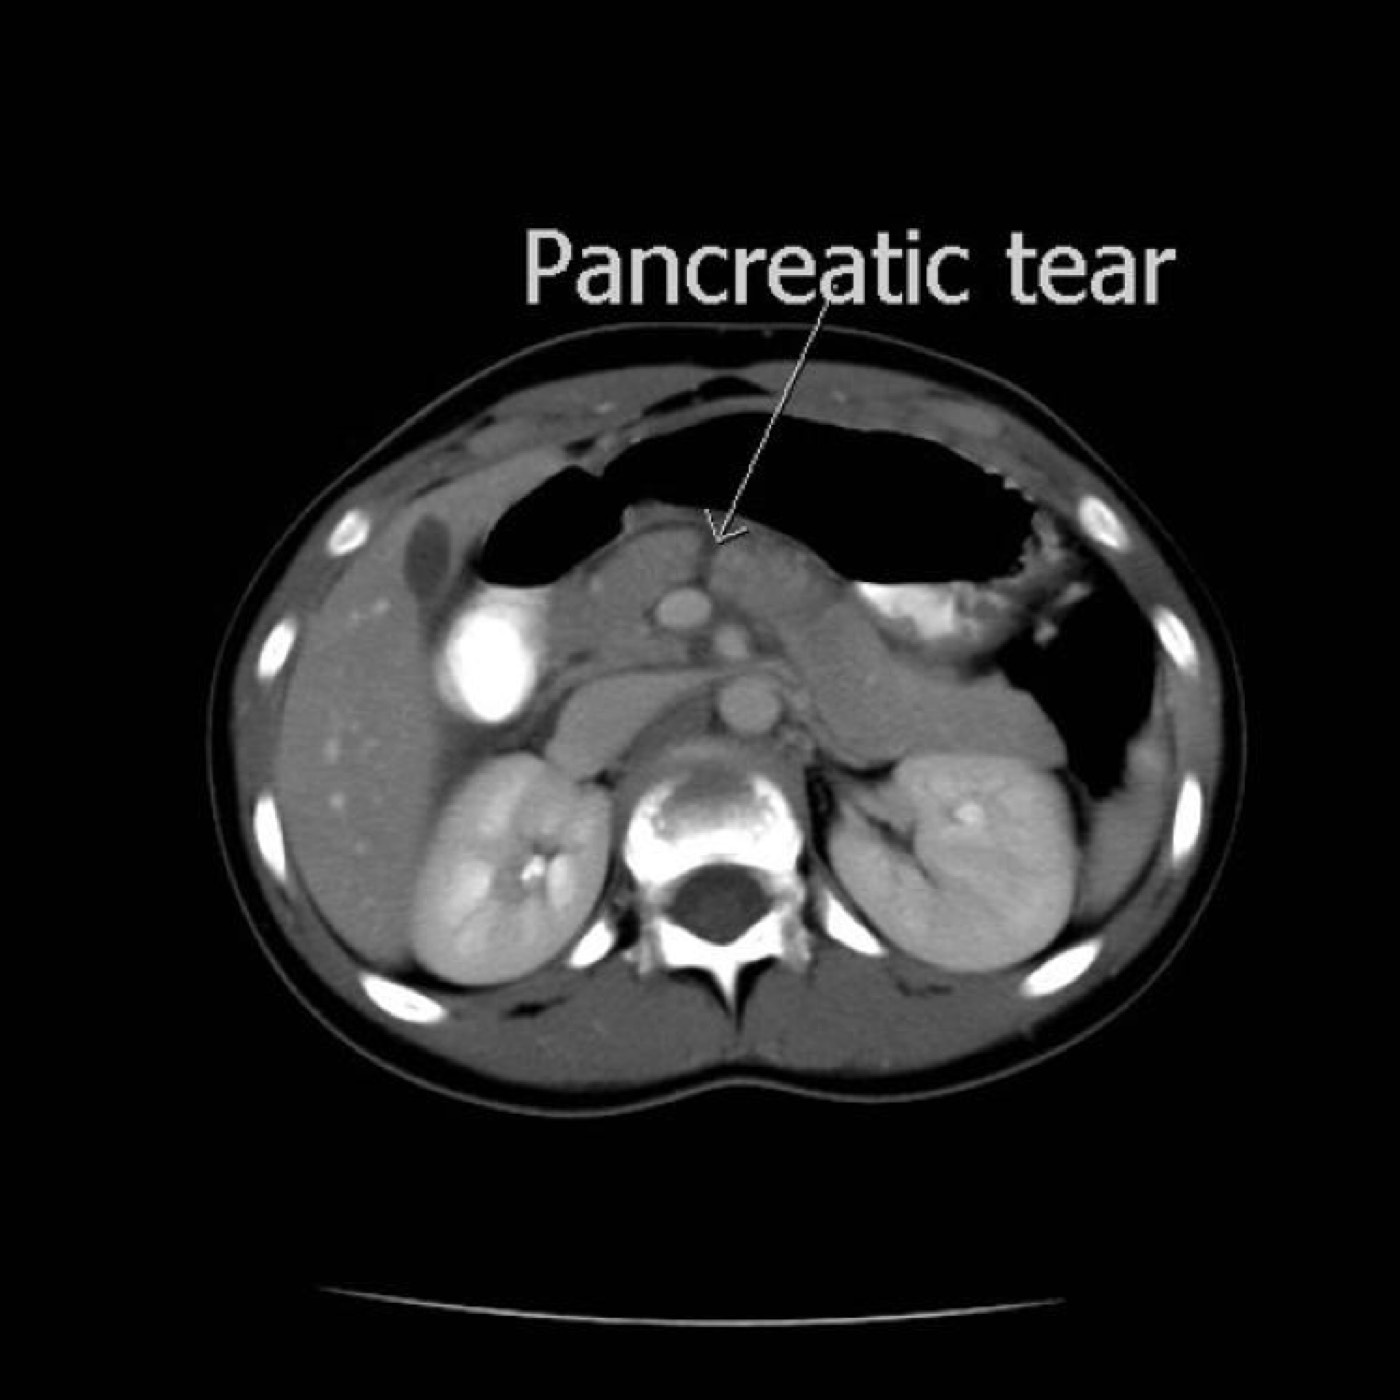

Contributors: Travis Barlock MD, Jeffrey Olson MS4 Feel free to use the cases below for your own practice. All of the scenarios are completely made up and designed to hit several teaching points. Case 1 25 M, presents to the ED with chest pain. Stabbing, started a few hours ago, substernal. Thinks it is GERD. After 2-3 minutes, pain worsens and radiates to the back. VS: BP 125/50 (Right arm 190/110). HR 120. RR of 18. Sat 98% on RA. Additional VS: Temp of 37.2, height of 6'5", BMI of 18. PMH: None, doesn't see a doctor. Meds: None FH: Weird heart thing (Mitral Valve Prolapse), weird lung thing (spontaneous pneumothorax), tall family members with long fingers and toes Physical Exam: Cards: Diastolic decrescendo at the RUSB, diminished S2. UE pulses are asymmetric, LE pulses are asymmetric, carotid pulses are asymmetric, BP is asymmetric MSK: Knees, elbows, and wrists are hypermobile. Imaging: CXR #1 normal, #2 widened mediastinum (no read yet but shows widened mediastinum), POCUS shows small effusion CTA/MRA doesn't come back until after the case. ECG: Sinus Tach Labs: NT-proBNP 500 pg/mL D-Dimer: 7000 ng/L CBC: Hemoglobin: 13.5 g/dL, WBC: 20,000/µL, Platelets: 250,000/µL Chem 7: Na 138, K, 5.7, Cl 102, Bicarb 17, BUN 45, Creatinine: 3.5 mg/dL, Glucose: 180 LFTs: Albumin 2.4, Total protein 5.5, ALP: 140, AST: 3500, ALT: 2800, TBili: 3.2, DirectBili: 2.4, Ca: 7.8 LDH: 2200 PT: 20.5, INR: 2.2, Fibrinogen: 170 5th gen High-Sensitivity Troponin: <3 Lactate: 7 mmol/L VBG: pH 7.22, paCO2 28, bicarb 15 Notes: Can have patient crash somewhere in middle and show 2nd xray Case 2: A 67-year-old female is brought to the ED by her daughter due to progressive weakness, confusion, and fatigue that have worsened over the past week. Unable to get out of bed and has become increasingly lethargic. Also having some nausea, constipation. The daughter denies any preceding illness, recent trauma, or travel. Does not know her meds but will head home to get them after talking with you. VS: BP 88/55 mmHg, HR 110, RR 20, O2 Sat 98% on room air. Additional VS: Temp 36.8°C. PMH: Hypertension, osteoarthritis, and depression. Physical exam: General: Thin, somnolent but arousable. HENT: Dry mucous membranes Neuro: Confused, A&Ox1 (self), hyporeflexia Labs (Includes many that would not return in the ED in case you want to take this case forward to the floor) CBC: WBC 9,500, Hb 16.5, Hct: 50%, Platelets 220,000 Chem7: Na 129, K 2.1, Cl 95, HCO3 34, Creatinine 1.6, BUN 40, Glucose 115 LFTs: normal Magnesium: 1.1 Calcium: 10.8 mg/dL (corrects to 12.8) iCal: 3.2 Phosphate: 2.3 mg/dL Albumin: 2 BUN:Cr ratio: 25 VBG: pH: 7.49, PaCO2 45, HCO3: 34 Lactate: 2.8 Serum Osmolality: 276 mOsm/kg (Osmolal gap of 2) Urine Osmolality: 550 mOsm/kg Urine Sodium (UNa): 10 mEq/L (low). Urine Potassium (UK): 25 mEq/L (elevated). Urine Chloride (UCl): 12 mEq/L (low). Urine Magnesium (UMg): 20 (Elevated). Urine Calcium (UCa): 50 in 24 hrs (Low) 100 cc of urine with foley FeNa Plasma renin activity: 15 mg/mL/hr (elevated), Aldosterone: 25 ng/dL (Elevated), ADH: Elevated, Diuretic screen: Positive for thiazides PTH: 8 (low), HsTrop: 32, Cortisol and ACTH: Normal. EKG: Hypokalemia features CXR: Normal Renal US: shows stones Improves with fluids Note: Can have daughter return with med list at some point including HCTZ, ibuprofen, and sertraline Case 3: Patient Presentation EMS Report: A 27-year-old male involved in a high-speed motorcycle collision is brought to the emergency department by EMS. The patient was found unconscious at the scene with evidence of severe thoracic and extremity trauma. He was intubated en route for airway protection due to altered mental status (GCS 7). VS: HR 130, BP 90/60, RR: bagging at 12 bpm, satting 88% on 100% FiO2 Primary Survey Airway: Endotracheal tube in place. Breathing: Decreased breath sounds on the left side with visible chest asymmetry and paradoxical chest wall movement. Circulation: Mottled extremities noted, with significant deformity of the right thigh. Pulses are diminished in the right leg Disability: GCS remains 7 (E1 V2 M4). Pupils equal and reactive. Exposure: Full-body examination reveals an open fracture of the right femur, multiple abrasions, and bruising over the chest wall. Vent alarms Peak Inspiratory Pressure (PIP) 40 cm H₂O (elevated) Plateau Pressure (Pplat) 35 cm H₂O (elevated) EtCO₂ (End-Tidal CO₂) 55 mmHg High-Pressure Alarm Triggering frequently Glucose 120 CBC: Hgb 8.9, Hct 27, WBC 14.2, platelets 220,000 VBG: pH 7.28, pCO2 33, bicarb 18, lactate 4.5 CXR with tension pneumothorax Patient improves after chest tube, pigtail catheter, or needle decompression. Ready to be transferred upstairs and O2 starts tanking again Vent alarms- second episode Peak Inspiratory Pressure (PIP) 35 cm H₂O (elevated) Plateau Pressure (Pplat) 30 cm H₂O (elevated) EtCO₂ (End-Tidal CO₂) 20 mmHg HR: 140, satting 84%, temp 38.5, ABG: pH 7.32, pCO₂ 30 mmHg, pO₂ 60 mmHg on 100% FiO₂, HCO₃⁻ 18 mmol/L (hypoxemia and metabolic acidosis). D-dimer: Elevated Thrombocytopenia: Platelets 90,000/µL. US shows blown right ventricle ECG shows new RBBB CT PE: Ground glass opacities, consolidation, centrilobular nodules, septal thickening, and fat-attenuating lesions. Note: Management is largely supportive care so once the diagnosis is made, end the case. References Carroll MF, Schade DS. A practical approach to hypercalcemia. Am Fam Physician. 2003 May 1;67(9):1959-66. PMID: 12751658. Coelho SG, Almeida AG. Marfan syndrome revisited: From genetics to the clinic. Rev Port Cardiol (Engl Ed). 2020 Apr;39(4):215-226. English, Portuguese. doi: 10.1016/j.repc.2019.09.008. Epub 2020 May 18. PMID: 32439107. Palmer BF. Metabolic complications associated with use of diuretics. Semin Nephrol. 2011 Nov;31(6):542-52. doi: 10.1016/j.semnephrol.2011.09.009. PMID: 22099511. Reed MJ. Diagnosis and management of acute aortic dissection in the emergency department. Br J Hosp Med (Lond). 2024 Apr 30;85(4):1-9. doi: 10.12968/hmed.2023.0366. PMID: 38708978. Roberts DJ, Leigh-Smith S, Faris PD, Blackmore C, Ball CG, Robertson HL, Dixon E, James MT, Kirkpatrick AW, Kortbeek JB, Stelfox HT. Clinical Presentation of Patients With Tension Pneumothorax: A Systematic Review. Ann Surg. 2015 Jun;261(6):1068-78. doi: 10.1097/SLA.0000000000001073. PMID: 25563887. Rothberg DL, Makarewich CA. Fat Embolism and Fat Embolism Syndrome. J Am Acad Orthop Surg. 2019 Apr 15;27(8):e346-e355. doi: 10.5435/JAAOS-D-17-00571. PMID: 30958807. Produced by Jeffrey Olson, MS4 Special thanks to Evan Fisch MD Get your tickets to Tox Talks Event, Sept 11, 2025: https://emergencymedicalminute.org/events-2/ Donate: https://emergencymedicalminute.org/donate/